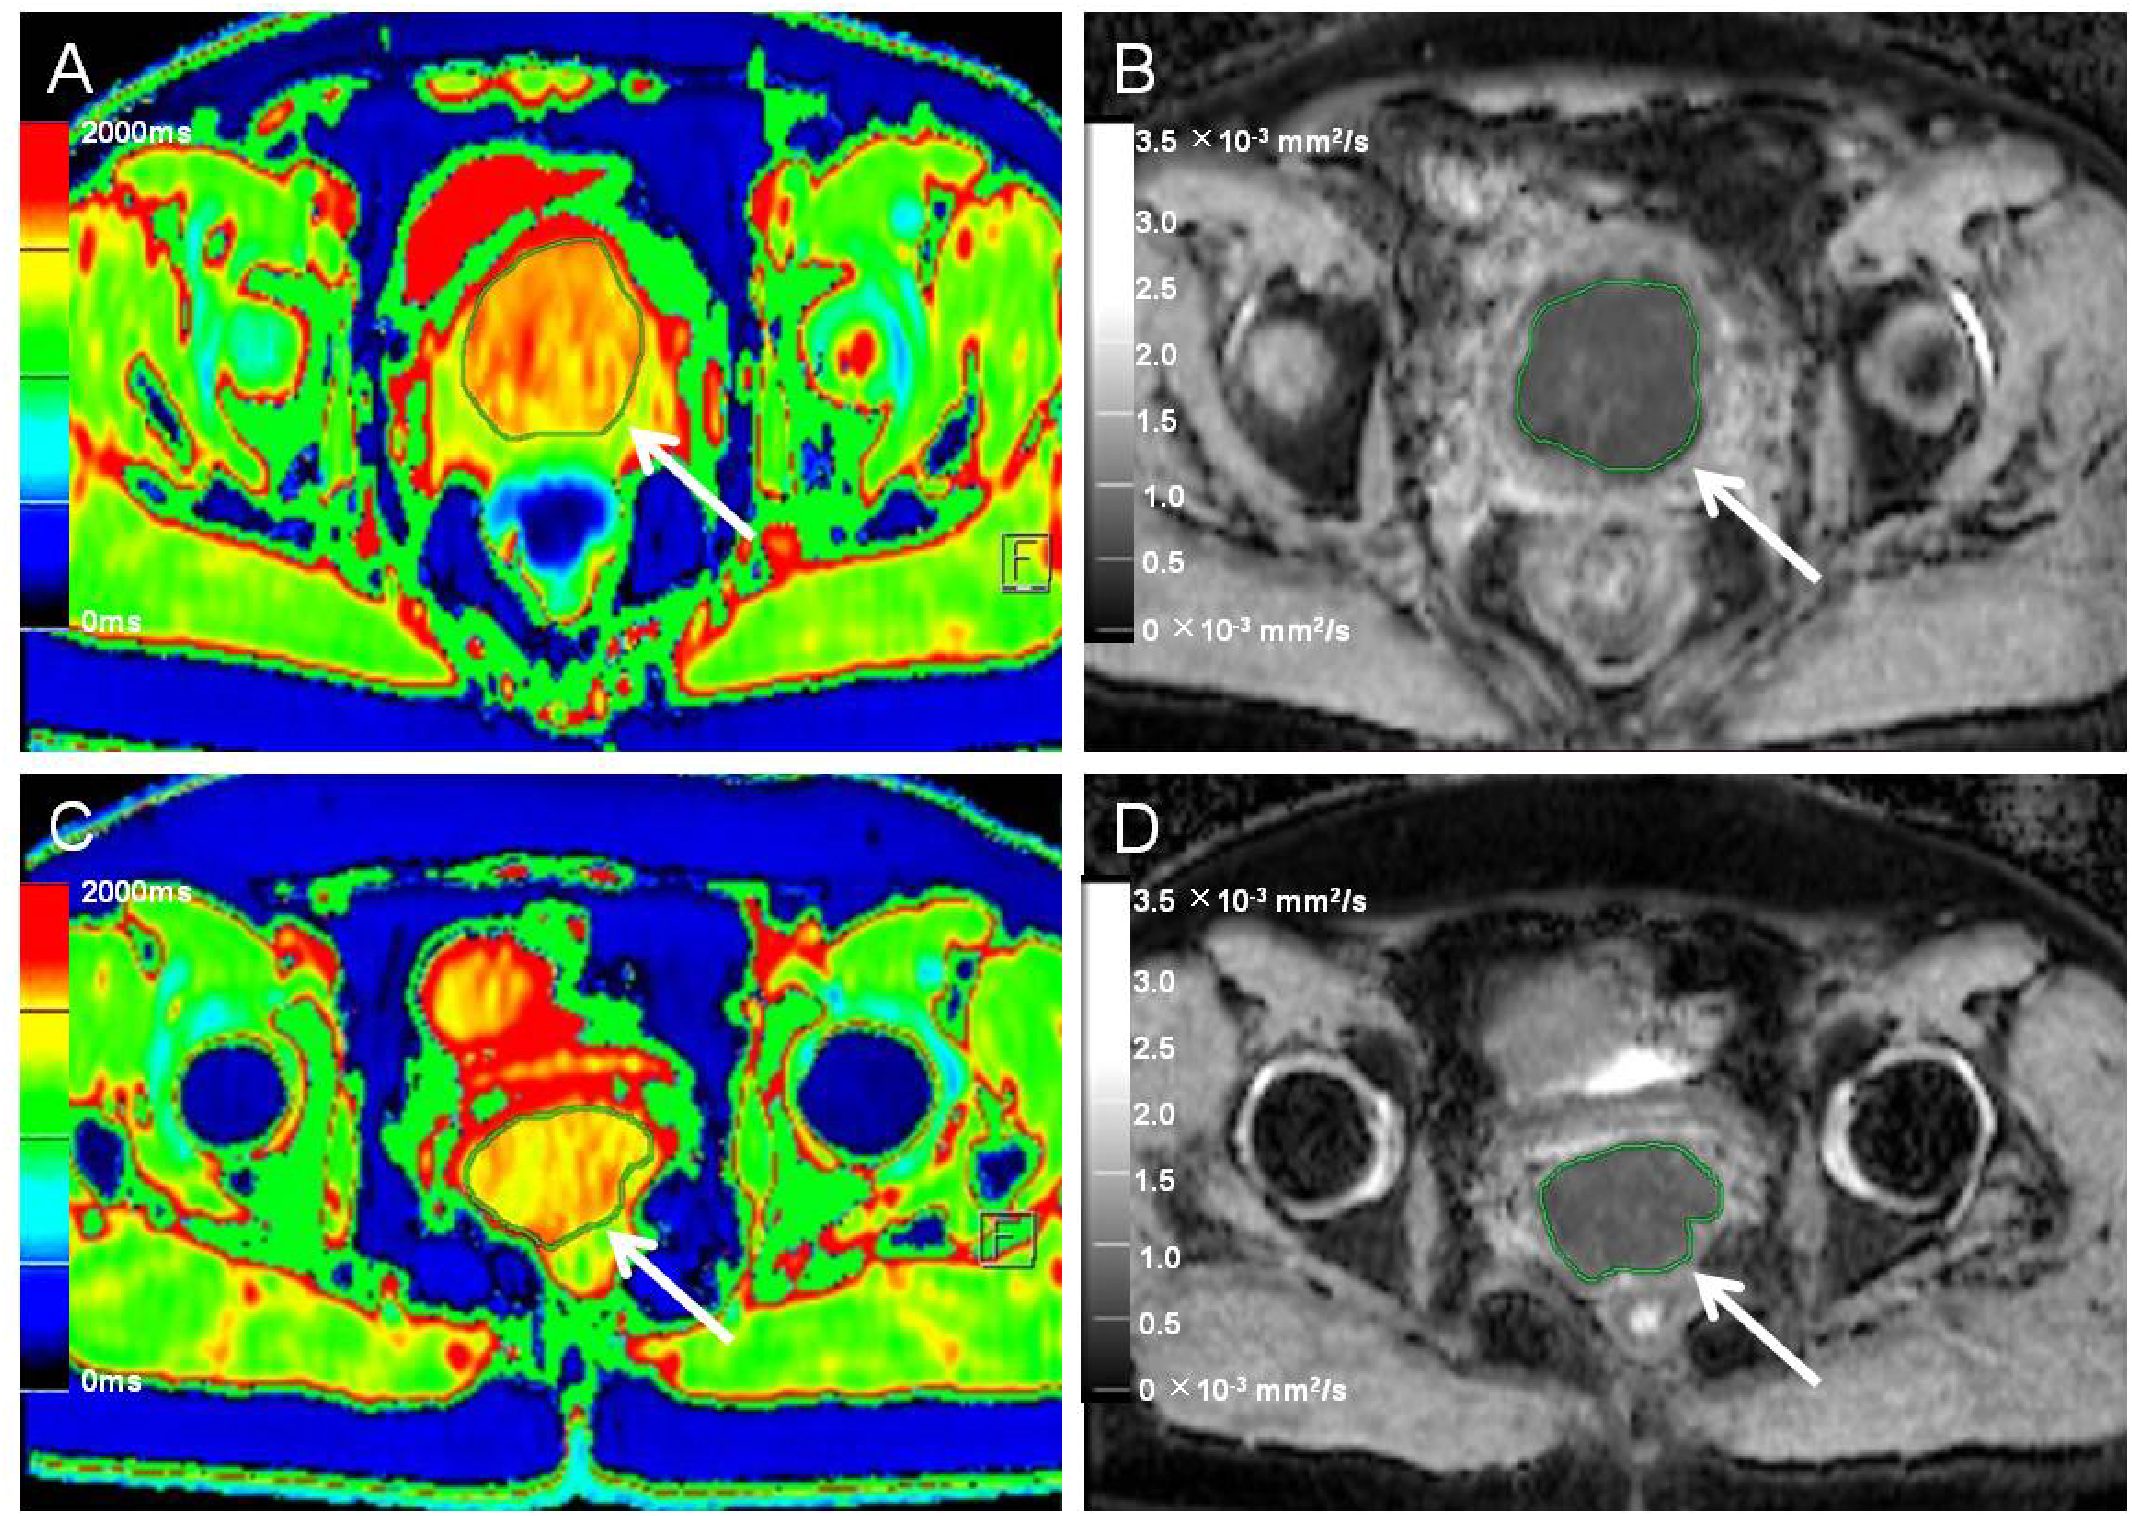

Figure 3

Native T1 mapping and apparent diffusion coefficient (ADC) images of recurrent and nonrecurrent cervical cancer (CC) in the non-surgical group. (A, B) A 55-year-old patient with recurrence during the follow-up period. (A) Axial T1 mapping pseudo-color map and (B) axial ADC image. The native T1 and ADC values were 1556.65 ms and 0.77 × 10−3 mm2/s, respectively. (C, D) A 51-year-old patient without recurrence during the follow-up period. (C) Axial T1 mapping pseudo-color map and (D) axial ADC image. The native T1 and ADC values were 1489.09 ms and 0.84 × 10−3 mm2/s, respectively. The white arrows in A–D indicate the locations of the lesions.